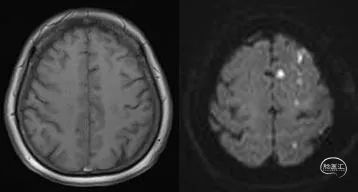

↑↑↑脑核磁提示梗死位于左侧内分水岭区域

患者转至监护室继续控制血压、脱水降颅压治疗,病情逐步好转。次日复查头颅核磁(图7),脑肿胀明显减轻,但DWI也提示在左侧半球散在点状高信号,核磁灌注成像(图8),双侧半球基本对称。TCD(图9)提示左侧半球血流速度正常。

图7:术后复查核磁